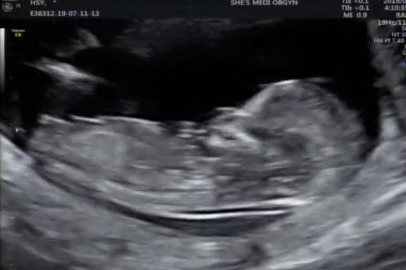

12주 차 목 투명대 검사 0.94mm

12주 차 목 투명대 검사에 아기 자세가 바르지 않으면 검사가 힘들다걱정이 무색할 정도로, 아기는 이미 알고 있다는 듯 '빨리 검사해주세요' 하는 자세로 얌전히 누워있어 의사 선생님의 칭찬과 함께 목 투명대 검사를 사히 통과했다. 벌써 엄마에게 받는 것보다 주는 것이 많은 아기인 것 같아 과연 내가 이 과분한 아기에게 좋은 엄마가 될 자격이 있을지를 생각하게 만든다.